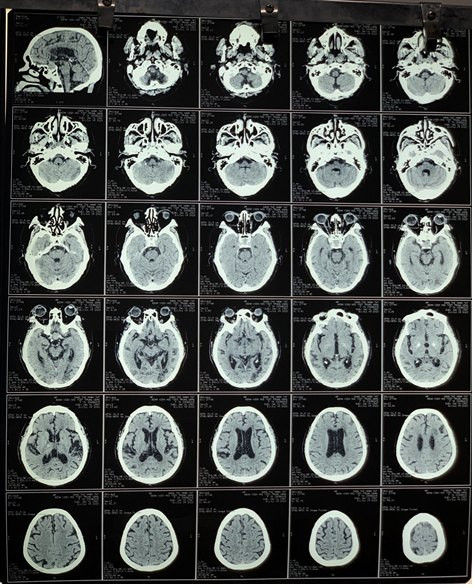

Chụp cắt lớp vi tính sọ não cho kết quả: Xuất huyết não cấp tính vùng đồi thị bên phải; các ổ tổn thương cũ nhân bèo và cạnh não thất bên bên trái.

| Xuất huyết não do tăng huyết áp cấp |